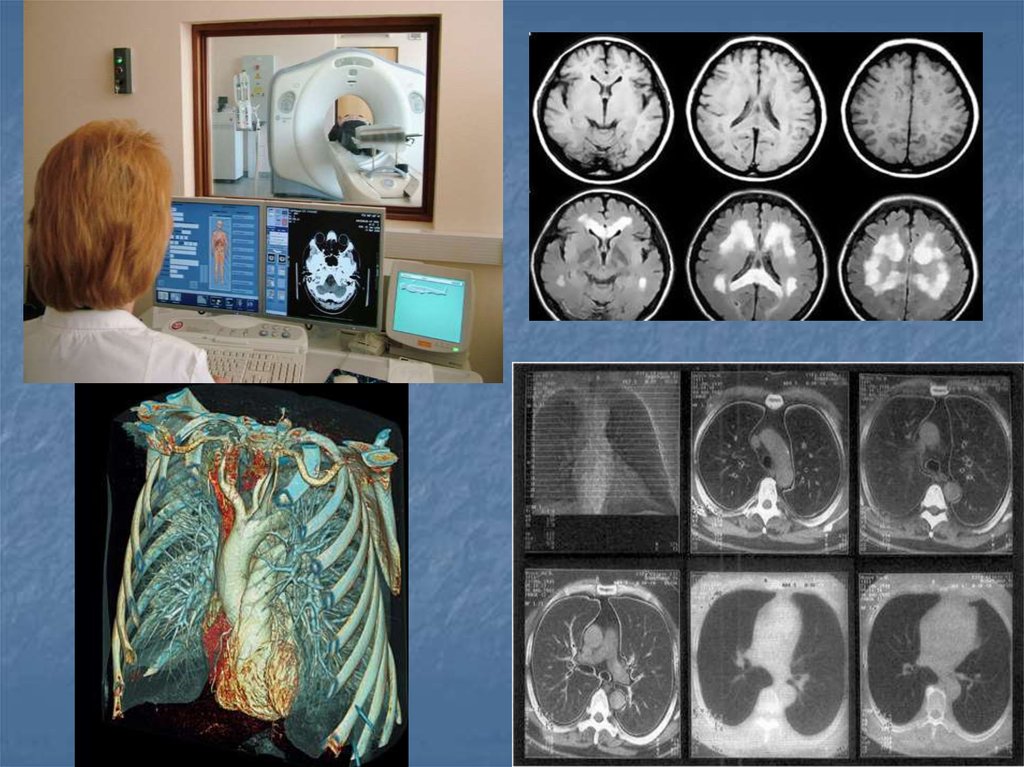

13. Показания

Опухоли и метастазы

Кисты, абсцессы и паразитарные кисты

Сочетанная травма

Воспалительные процессы(пневмония,

селликозы, гепатиты, артрозы)

16. Показания

Заболевания головного мозга,

2. Исследования функций отделов головного мозга,

3. Заболевания суставов,

4. Заболевания спинного мозга,

5. Заболевания внутренних органов брюшной

полости,

6. Заболевания системы мочевыведения и

воспроизводства,

7. Заболевания средостения и сердца,

8. Заболевания сосудов.